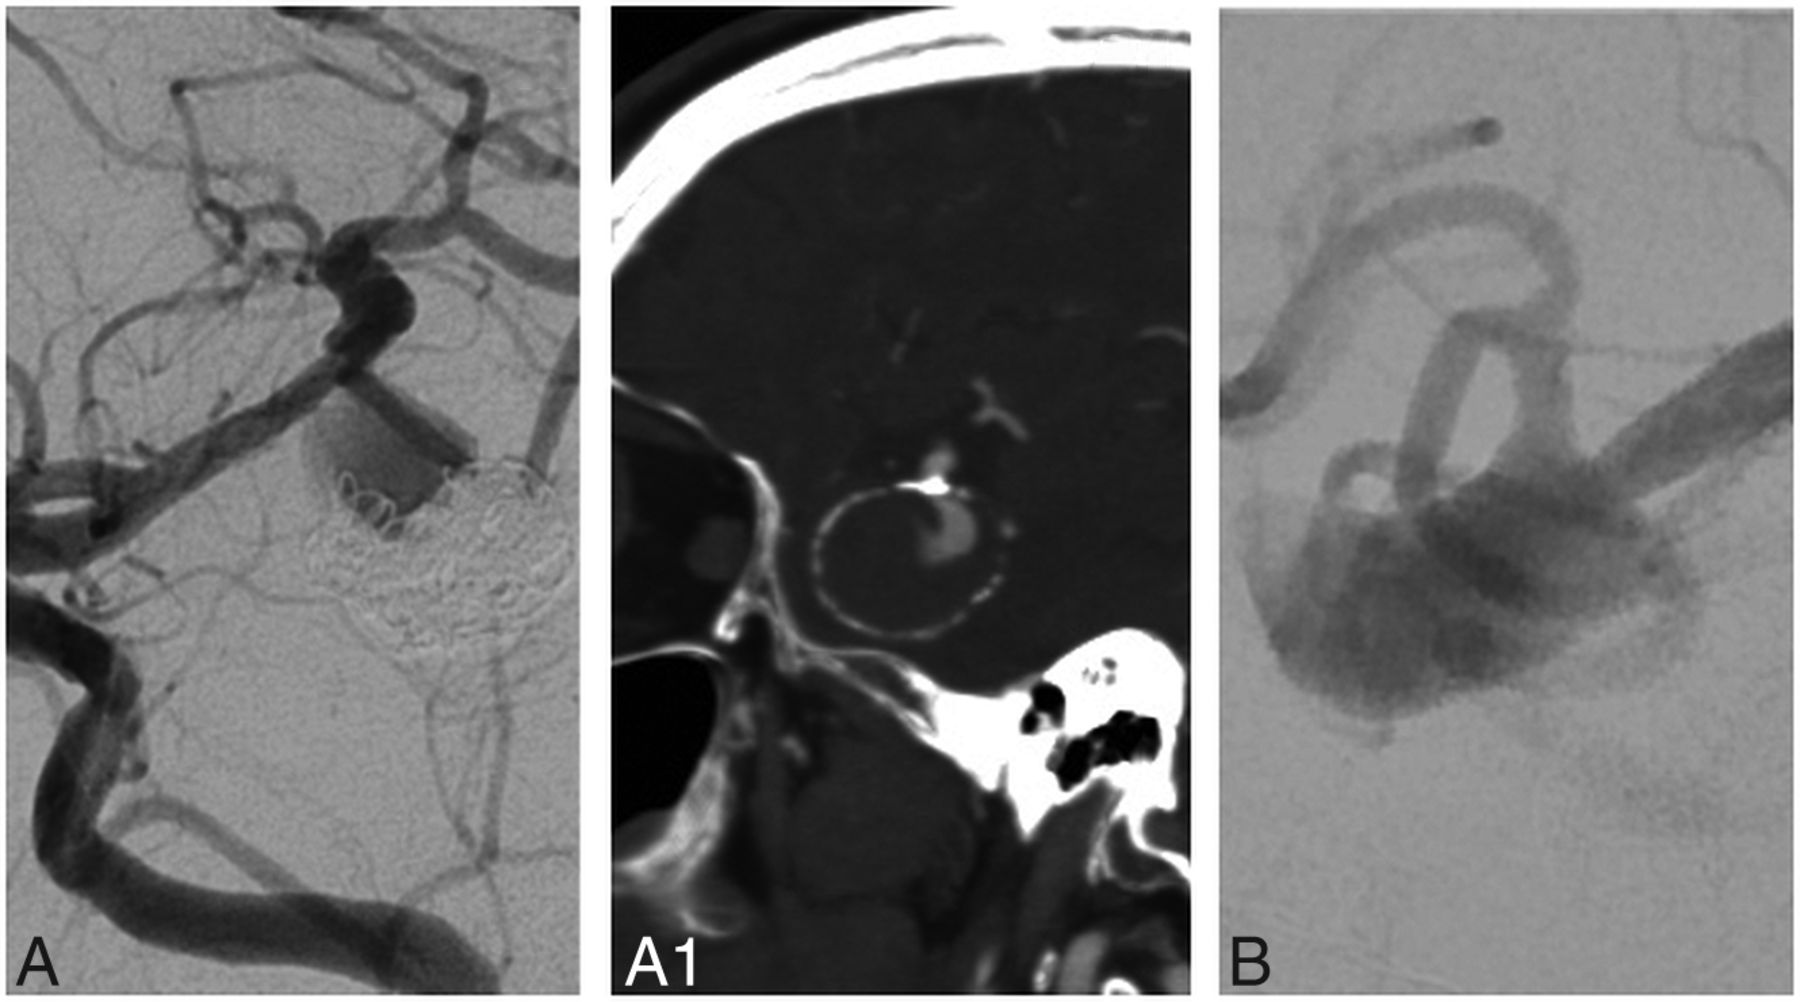

Patient and aneurysm characteristics included in the portfolio are detailed in the Online Supplemental Data, with typical cases depicted in Fig 1, and more difficult cases, in Fig 2.

Cases of high (A and B) and low (C and D) agreement: Seventy-seven percent of respondents selected surgical management for case A and 87% selected endovascular management for case B, while 51% and 49% selected surgical management for C and D.